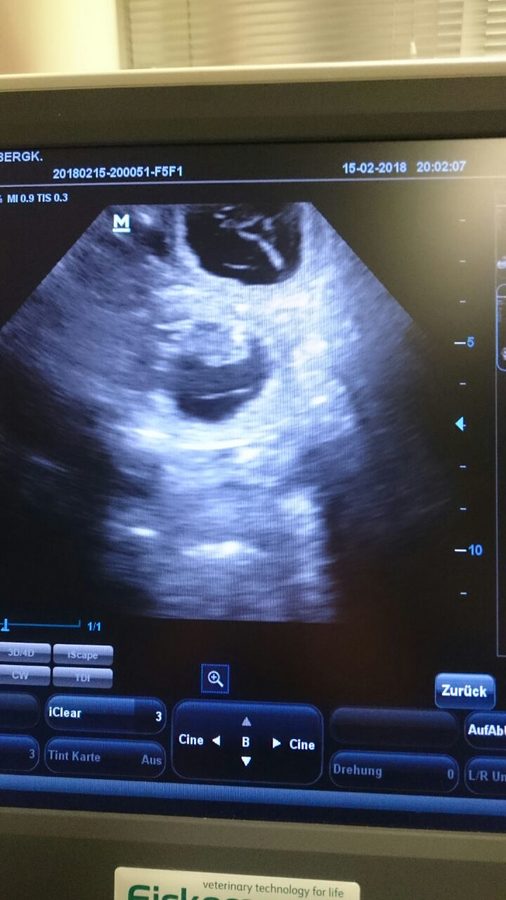

YUHUU, Fayola ist trächtig und wir erwarten unseren A- Wurf um den 20.03.2018!!!